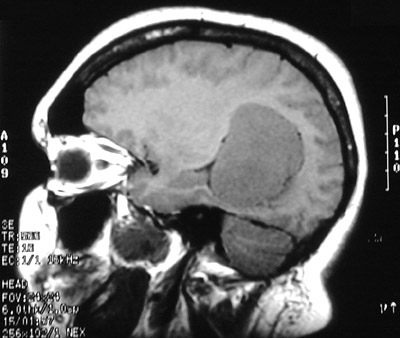

| The T1 weighted MRI scan in axial view above demonstrates another less common location for a meningioma, an intraventricular meningioma. In this location, a circumscribed mass could also be an ependymoma. Below can be seen the same right lateral ventricular mass with contrast enhancement in T2 weighted axial view and T1 weighted coronal view. |